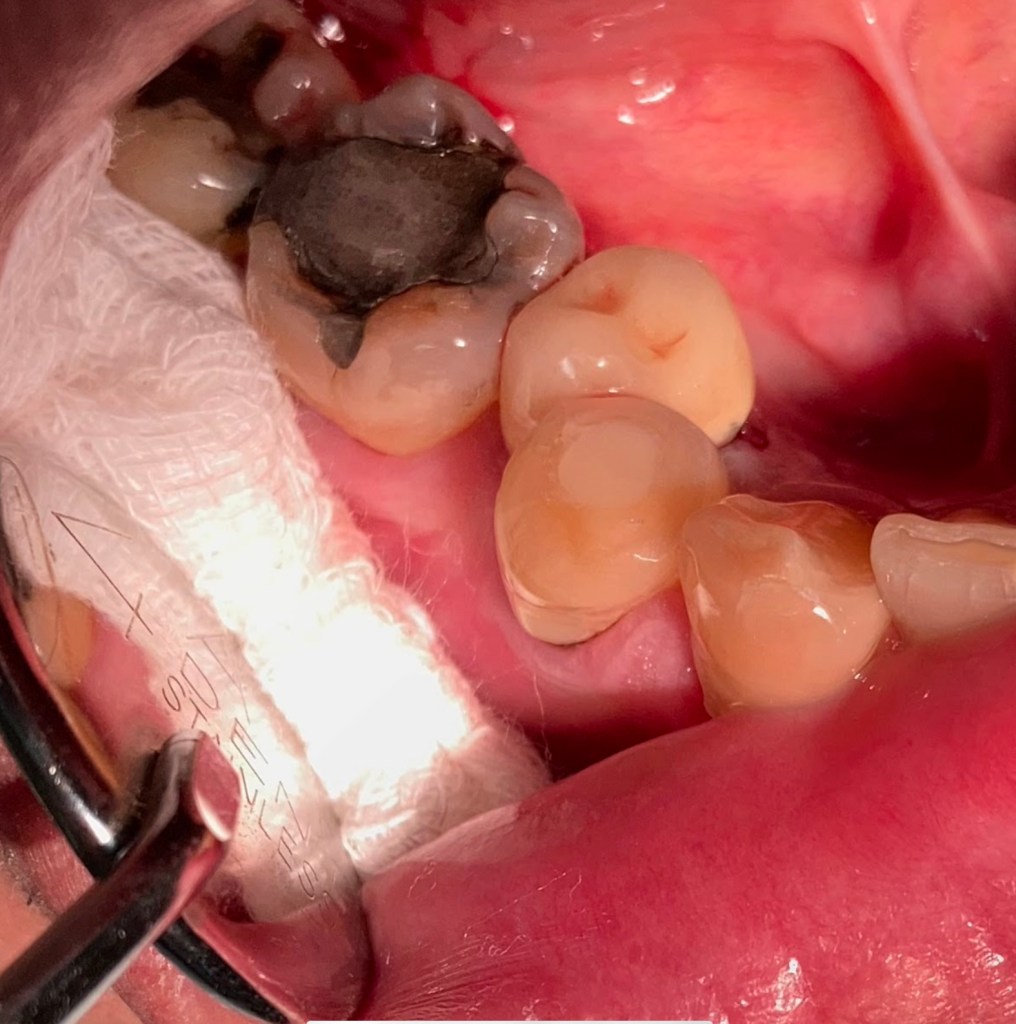

Don’t Remove. (before X-ray) radix-ento พบได้ในคนไทย 12.7% Germination X-ray ช่วยให้เห็นสิ่งที่ซ่อนอยู่ภายใน สังเกต furcation ก็รู้ว่าฟัน Perio Mermaid Premolar ให้สังเกตที่ mouth mirror เห็นถึงความฝ้ามัว เป็น Br พม่าครับ alloy ไม่แข็งมาก X-ray เท่านั้นจึงจะรื้อได้ ผมจะชอบวัดความยาวของฟันบ่อยๆ เทียบกับความยาวในใจที่เดาเอาไว้ RCT incomplete ใครสังเกตเห็นความผิดปกติบ้างครับ? ถึงกับต้องถ่ายทุกมุมเลยซี่นี้ remove ฟัน Crowding เป็น PVC ล้อมด้วยฟัน RCT อย่าลืม X-ray ก่อนถอนนะครับ Share this: Share on X (Opens in new window) X Share on Facebook (Opens in new window) Facebook Like Loading... Uncategorized